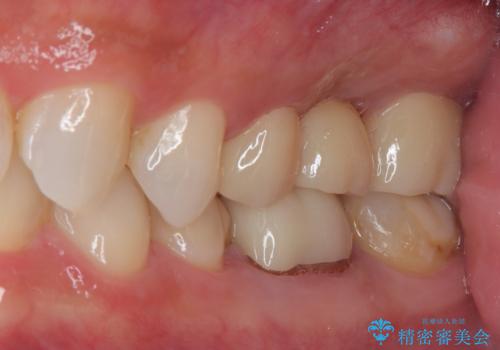

審美面、機能面ともに満足していただけました。

咬み合わせが強い方なので夜間にマウスピースを使ってもらいながら、メインテナンスで通ってもらう予定です。